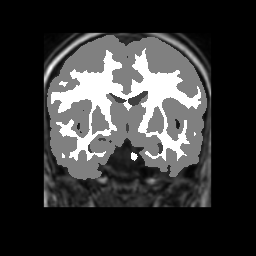

Accuracy is reported as Dice overlaps between a tool's segmentation and the Internet Brain Segmentation Repository (IBSR) manual segmentation for each of the 18 IBSR subjects. The inter-tool comparison (on the left below) shows the median Dice coefficient for each tissue class. The overlaps for FSL (from which the median values are drawn) are shown in the plot on the right.

Subject Accuracy (IBSR)

Overlap coefficients for each tissue class are shown here for each IBSR subject. Select a subject below to see the FSL results compared to other tools.